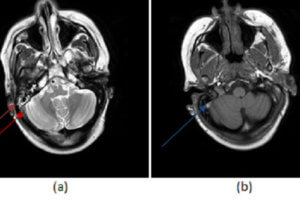

Carotid Artery Dissection, MRA

Carotid/vertebral artery dissection is an underdiagnosed disease that can result in substantial morbidity. It has an incidence of 1-1.5/100000 and disproportionately affects young patients. Diagnosis is challenging clinically because the symptoms are... Read more »

Vertebral Artery Dissection, CTA